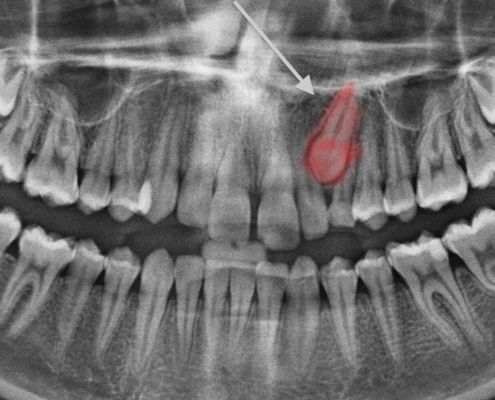

Résection apicale ou APICOECTOMIE